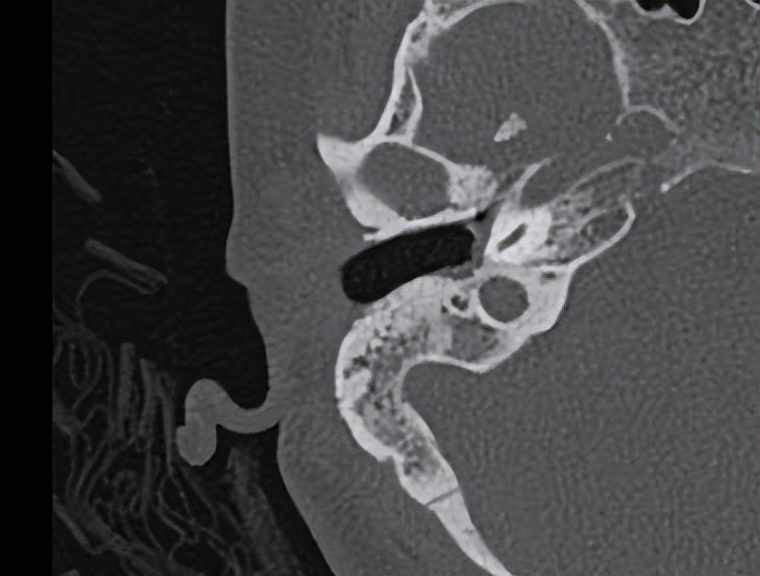

入院检查后发现谢女士的中耳有大量的钙化斑和肉芽组织,这是导致她反复流脓和听力极差的原因。这次做的是全麻耳内镜中耳炎微创手术,术中清理了钙化组织和肉芽后发现患者的听骨链是断裂的,术中取出了残留的锤骨和砧骨。镫骨是完整的,活动可。用人工听骨重建了听骨链,自体耳屏软骨修补了鼓膜。整个的手术用时约70分钟,非常的顺利。术后查房患者感觉听力有提高,无手术相关的并发症。